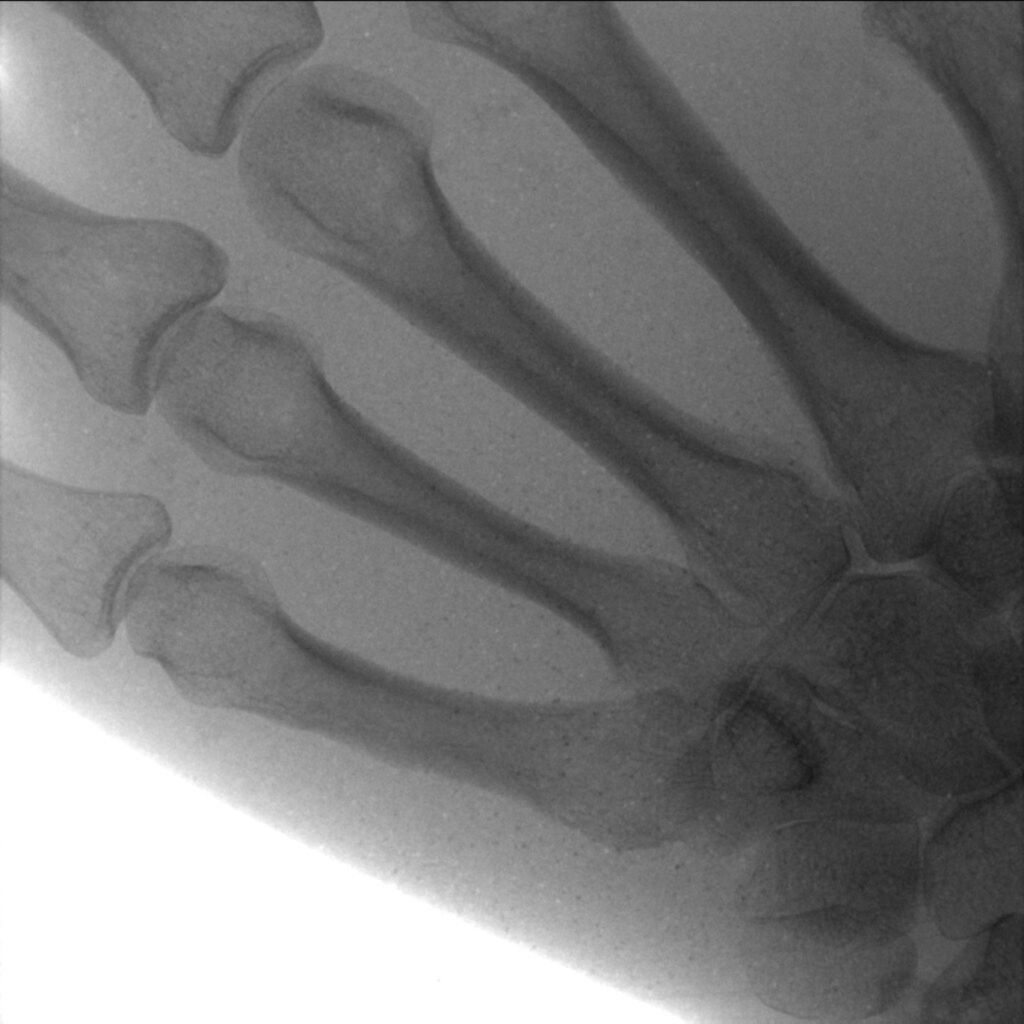

Direct conversion X-ray sensors, particularly suited for the detection of soft X-rays, are extensively utilized in medical imaging, notably in mammography and dentistry applications. Concerning statistics show that, currently, one out of eight women get a false-negative mammography result and 50% of women undergoing regular screening will receive a false-positive. Heavy metal-based quantum dots such as lead sulfide (PbS) are able to resolve this problem thanks to their unique properties. Their sensitivity to X-rays is up to ten times higher than the current industry standard of amorphous selenium (a-Se). This heightened sensitivity ensures superior image resolution, especially in low-dosage applications like mammography and promises significant improvements in diagnostic accuracy, essential for both patients and healthcare professionals. Unlike a-Se, the fabrication of amorphous quantum dot layers is a straightforward process that does not require sophisticated techniques. Quantum dots is a solution-processable material, simplifying the device fabrication process and enabling seamless scalability.